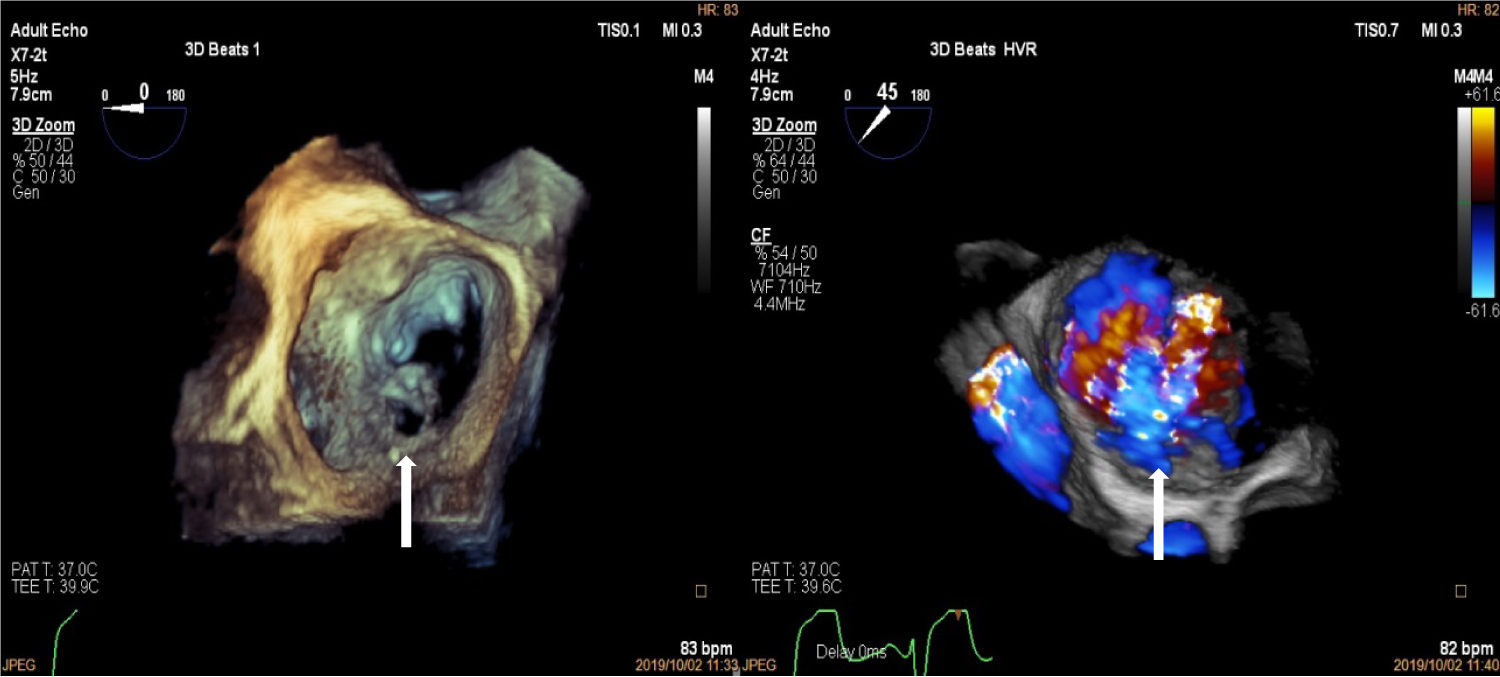

Upon arrival to the cardiology clinic, the patient was noted to be hemodynamically stable with a blood pressure of 126/83 mmHg and heart rate of 88 beats/min. He was not in heart failure. He had a displaced, volume overloaded apex beat and a grade 5/6 pan-systolic mitral regurgitation murmur. Twelve lead electrocardiograms showed sinus rhythm with wide P wave suggestive of left atrial enlargement and early repolarisation. His blood parameters revealed improved Haemoglobin at 11.1 g/dl, CRP of 37 mg/l and a normal urea and electrolytes. He underwent trans-thoracic echocardiography (TTE), which revealed a left ventricular end-diastolic diameter of 62 mm and left ventricular end- systolic diameter of 34.7 mm with an EF of 65%. Right ventricular systolic function was preserved with a trans-annular planar systolic excursion of 2.6 cm and RV S' velocity of 15.5 cm/s. There was severe eccentric mitral regurgitation and severe tricuspid regurgitation with an estimated pulmonary artery systolic pressure of 82 mmHg. No masses or vegetation's were noted. Two discrete aneurysms were noted, one just below the mitral annulus inferior to the posterior mitral leaflet (PML) and the second at the apex of the left ventricle (Figure 1). The patient subsequently underwent two dimensional and three- dimensional transoesophageal echocardiogram (TEE) which confirmed the presence of sub-mitral aneurysm and apical aneurysm. There was spontaneous echo contrast and thrombus in the sub-mitral aneurysm (Figure 2). The PML was perforated revealing two mitral regurgitation jets, one through the perforation and the second was central in origin (Figure 3 and Figure 4). There was also suspicion of oscillating mass on the PML (Figure 3). His blood cultures remained negative. The gene expert for Tuberculosis was negative. He tested negative for syphilis, Human immunodeficiency virus, connective tissue disease and sarcoidosis using the Treponema Haemagglutination test, HIV serology, antinuclear antibody test and serum angiotensin converting enzyme assays, respectively. The patient underwent Multi-detector Computed Tomography (MDCT) to define in detail the anatomical course of the aneurysms and also to exclude coronary artery disease. Multiple left ventricular aneurysms were noted in the posterior wall and the apex (Figure 5 and Figure 6). Aneurysm in the mid-postero-lateral wall measured 38.9 mm × 16.6 mm, sub-mitral aneurysm with thrombus in situ, measured 57.5 mm × 37.8 mm and it dipped inferior to the left atrium (Figure 6). The apical aneurysm in the inferior aspect was calcified at the antero-lateral margin and measured 54.4 mm × 12.7 mm, and in the septal aspect measured 26.9 mm × 14.7 mm. A discrete perforation was noted in the PML measuring 11.1 mm in diameter (Figure 5). There was no significant mediastinal lymphadenopathy.

Figure 4: Three-Dimensional Transoesophageal echocardiogram showing "enface view" of the mitral valve with perforation in the P1 segment of the mitral valve (left, white arrow) and three dimensional colour showing mitral regurgitation jet through posterior mitral leaflet perforation (right, white arrow). View Figure 4

Initial TTE imaging revealed mitral regurgitation due to prolapse of PML and concurrent sub-mitral aneurysm as well as apical aneurysm, but further definition of the aneurysm extent and presence of vegetation's was not possible. TEE proved useful in further confirming the aneurysms [9]. Three-dimensional TEE was useful in assessing the morphology of the valve and the enface view showed a clear perforation in the P1 segment of the PML [10]. On multiplane 3D reconstruction the area of the defect in the PML could be measured. Further, two distinct MR jets were visualised on 2D and 3D TEE. One was central due to annular dilation and the second eccentric jet was noted to be coming through the perforation, hence, confirming the presence of a true defect in the mitral valve and not merely an artifact. The suspicion of oscillating mass was raised after TEE imaging due to the superior imaging quality and good temporal resolution of TEE. Finally, MDCT through its good spatial resolution enabled visualisation of the location and anatomy of the aneurysms as well as presence of clear perforation in the PML [11]. It also non-invasively confirmed normal coronary anatomy, thus excluding this as a cause of the left ventricular aneurysms. It established presence of thrombus in the sub-mitral and the apical aneurysm which was not clearly delineated on TEE.